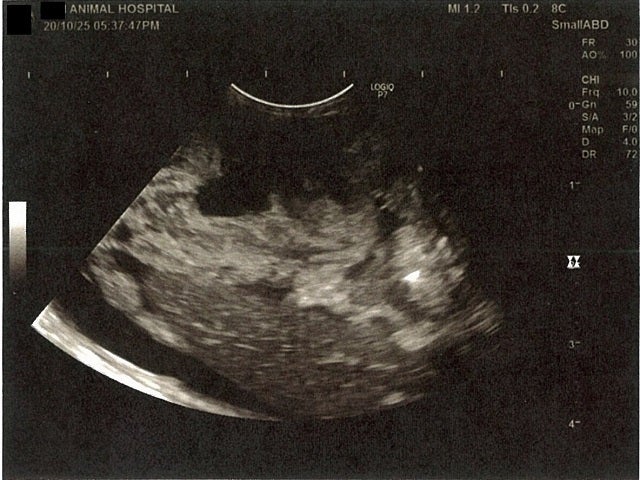

《心臓周りの胸部以外の全ての腹部で腹水がみられるとの診断です》

大網という部分で内臓を包む膜のようなものです。その周りに腹水が溜まっています。

左腎臓周りに腹水が確認できるエコー写真